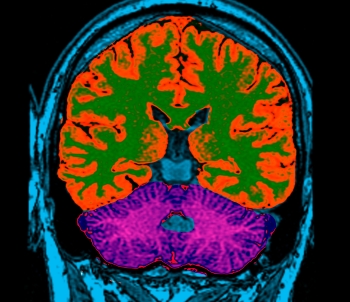

Creierul inca ne fascineaza, fie ca suntem oameni de stiinta sau simpli trecatori prin viata. De multe ori, il putem pacali printr-o serie de experimente care ne amuza si ne fascineaza in egala masura...